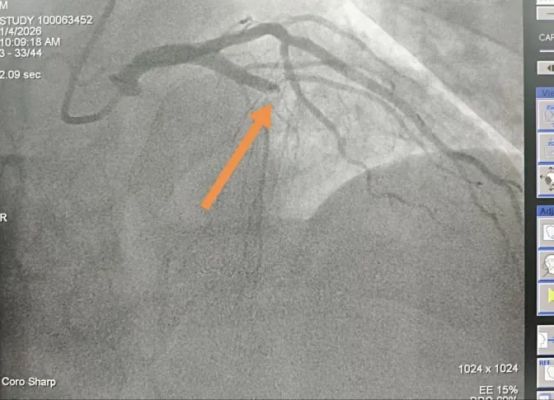

在120急救车医护人员的密切监护转运下,患者顺利转入西安市第九医院手术室,西安市第九医院介入医师团队提前做好术前准备,接到患者后立即为患者进行冠状动脉造影,PCI术中显示:“前降支闭塞”,成功植入支架一枚,堵塞的血管得以重新通畅,送患者至西安市第九医院,120急救车9:43到达该院大门时心内科会诊医生已提前在大门口等待,到院后绕行急诊科、CCU,第一时间直达介入导管室,心内介入手术团队接到患者后立即为患者进行急诊冠脉造影显示:冠脉多支多段重度病变,LAD近端完全闭塞,10:16导丝顺利通过,药物支架1枚干预LAD近端病变,D2W时间33分钟。

图为患者介入手术前后的心脏造影